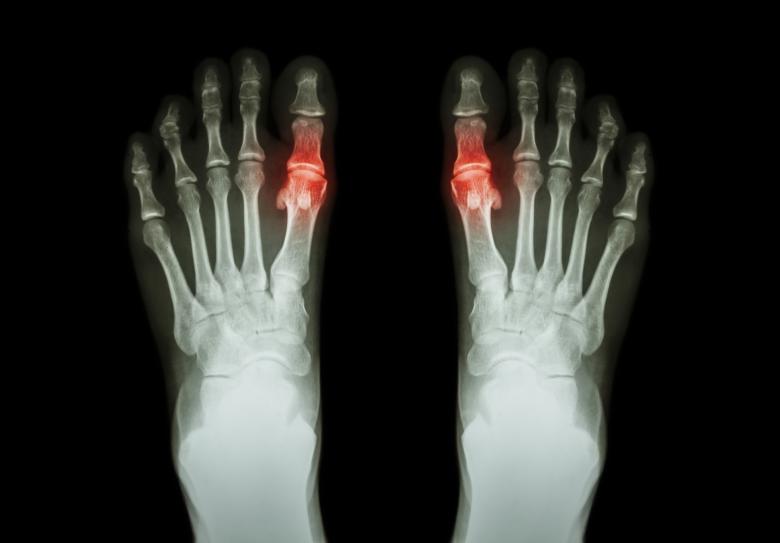

Dna, jinak také pakostnice, je revmatologické zánětlivé onemocnění, jehož projevy se mohou objevovat při dlouhodobě vysokém přísunu purinů do těla. Jedná se o látky, které jsou obsaženy hlavně ve stravě bohaté na bílkoviny. Tato choroba, dříve také nazývaná „nemoc králů“ nebo „nemoc bohatých“, se projevuje v návaznosti na tzv. hyperurikemii, což je zvýšená hladina kyseliny močové. Ta může být způsobena zvýšenou produkcí kyseliny močové při maligních onemocněních, nedostatečným vylučováním v důsledku poklesu ledvinných funkcí, nadměrnou konzumací alkoholu a nápojů slazených fruktózou. Zvýšená hladina kyseliny močové v krvi zpravidla vede k ukládání krystalů její soli do šlach, kloubů (dnavá artritida) a ledvin (dnavá nefropatie). Ty poté mohou vyvolat silně bolestivé zarudnutí, které může přejít do akutního dnavého záchvatu.

Pakostnice nejčastěji postihuje palec u nohy. „Postižené místo bývá horké, oteklé, velmi zarudlé a bolestivé. Kůže bývá napjatá a lesklá, čemuž se říká „fenomén zrcátka“. Nástup dnavého záchvatu může být doprovázen horečkou a dochází k němu nejčastěji v noci nebo časných ranních hodinách. Může trvat několik hodin nebo několik týdnů, obvykle trvá 7–14 dnů. Bolest i otok poté sice ustoupí, ale samotná nemoc v těle zůstává. Dnavý záchvat může proběhnout pouze jednou za život, ale také se může v budoucnu opakovat,” uvádí Lánová.